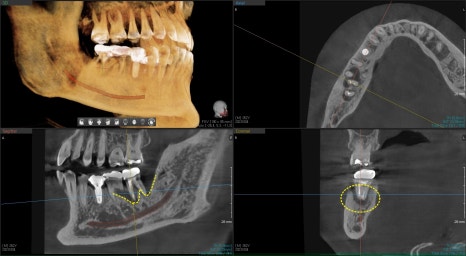

뿌리 주변 염증에 의해 발치가 필요한 경우입니다

3D CT를 촬영해보니

가장 큰 뿌리 주변이 염증에 의해 뼈가 녹아있습니다

빨간선으로 표시된부분이 뼈로 채워져 있어야하지만

어둡게 보이는것은 염증으로 뼈가 녹았다는것을 보여줍니다.

이런경우 발치와 동시에 즉시 임플란트 수술이 가능은 하지만 추후 뼈가 어디까지 회복될지 예측이 어려웠기 때문에 발치를 했던 주변으로 치조골이식을 해서 볼륨을 유지시켜주는것을 발치와 보존술이라고 합니다

약 4개월후 빨간선으로 표시된것 처럼 주변 뼈들이 회복이 된것을 확인 후 임플란트 수술이 진행되었습니다.

이렇게 벽을 이루고 있는 뼈들이 녹아있는경우는 치조골 이식후 회복기간을 기다렸다 하는경우가 예측이 좀더 좋습니다